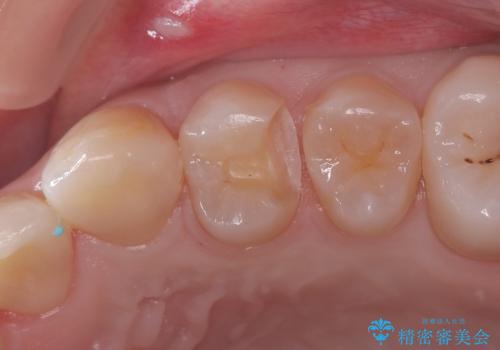

歯肉に炎症がない事を確認してセラミッククラウンにて治療を行っています。

最終的な被せものをする前に歯肉に炎症がないかを確認する必要があります。

炎症が残っている場合には歯周外科を提案する場合もあります。